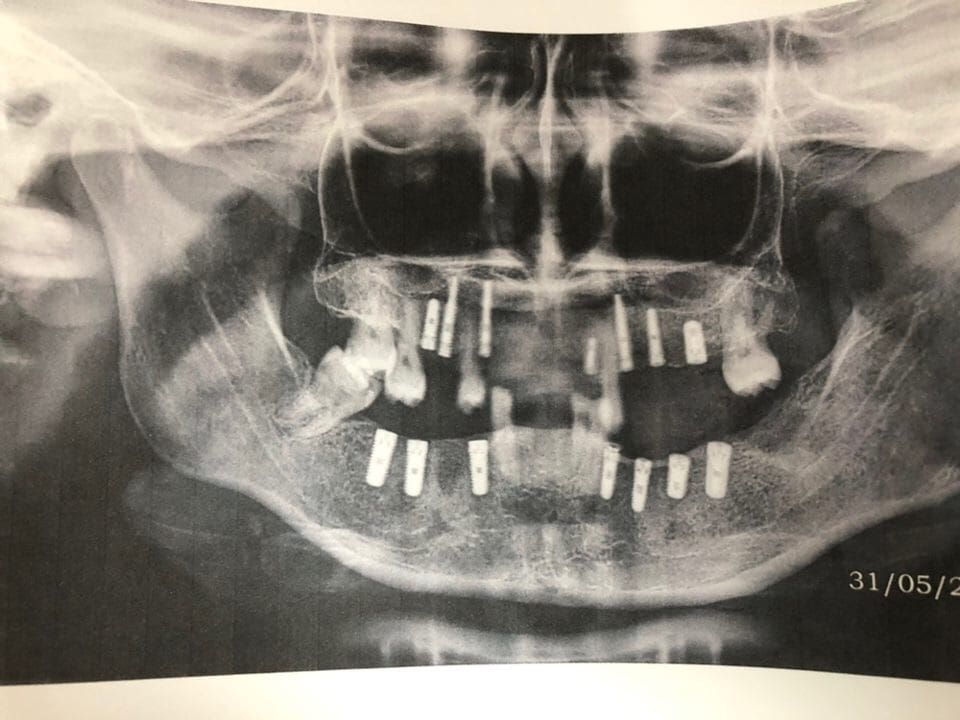

I found my assigned chair and met my partner, Dr. Konstantine Malafi from Queens, New York. The surgeon working with us was Dr. Toro, a humble yet incredibly accomplished surgeon who can place sutures with a skill that I have never before witnessed. The day began with a brief description of the surgical protocol, and then I was handed a chart. All patients had been previously screened for health histories and cone beam CT scans were taken to identify where the implants were to be placed. Before I could look up, a patient was sitting in the chair, just smiling up at me. And so the day began. We reflected flaps, we expanded ridges, we placed implants, we placed sutures. We dismissed a patient only to turn around and find another one already in our chair. Some patients only received one implant, some patients received as many as seven. All patients left the chair saying, “Gracias”. Before I knew it, it was 9:20pm and the chairs in the make-shift waiting area at the end of the clinic floor were finally empty. Konstantine had placed ten implants and I had placed nine. I collapsed on the bus back to the hotel, feeling that high that you only get from being in some kind of long endurance activity, like running a marathon. Only I was more tired than that. This was exhausting and exhilarating and overwhelming all at the same time.

I returned to the clinic the following morning to have a patient already waiting in the chair. Noticeably, I did not feel as nervous as the day before. I knew what to expect, and looked forward to the work. The day flew by again, finishing at 7:20pm this time. Konstantine had placed nine implants and I placed another nine. The third day, Konstantine and I finished our fortieth implant at 10:30am. What an experience!